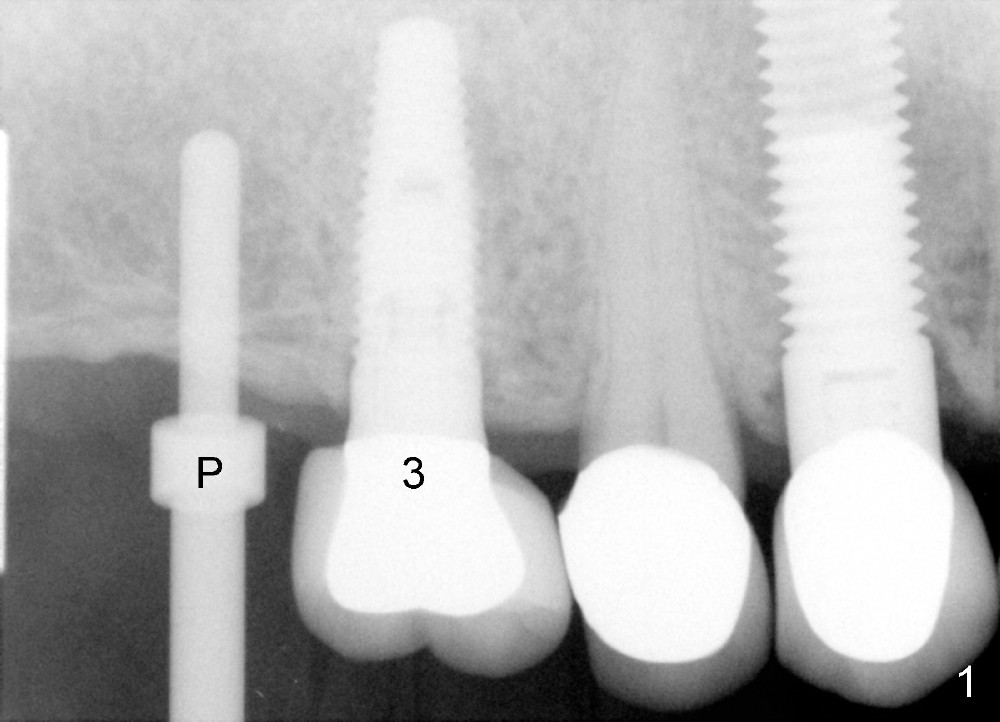

Analysis of preop PA suggests that the density of the cancellous bone is low at the site of the tooth #2. It is confirmed when a 2 mm pilot drill is used to initiate osteotomy. There is no drilling resistance once the pilot drill penetrates the cortex. A parallel pin is inserted for trajectory (Fig.1: P; 8 mm deep). The osteotomy is slightly moved distally with Lindermann bur and enlarged by inserting Bone Expanders from 2.6 to 3.8 mm at the depth of 12 mm (Fig.2). The osteotomy is then intended to move mesially and the depth is increased to 14 mm. Finally a 5.3x14 mm submerged implant is placed with insertion torque ~ 40 Ncm (Fig.3). The implant looks to have been tightly engaged into the bone (Fig.4). In one word, minimal bone removal is required for implant placement in the soft bone, particularly in the maxillary posterior region. A 8.2 mm healing abutment is placed; the flaps are closed by Chromic gut suture and perio glue (Fig.5). The wound heals normally 1 week postop (Fig.6). Fig.7 shows X-ray 3 months postop (H: healing abutment). Soft tissue looks healthy 4 months postop before (Fig.8) and after (Fig.9) removal of the healing abutment for restoration. There is no bone loss 7 months post cementation and 11 months postop (Fig.10 C: crown). It appears that bone expansion prevents bone resorption. There is no bone resorption 1 year 9 months post cementation. The implant is functioning 3 years 9 months post cementation (Fig.11).